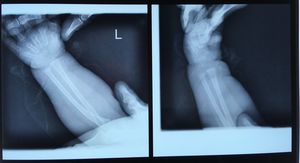

1y 3mo girl , with frontal bossing and blue sclera , maybe Fe deficiency , w:7400gr , h:70cm , Ca:9.9 , P:4.9

Osteogenesis Imperfecta?

No , rickets